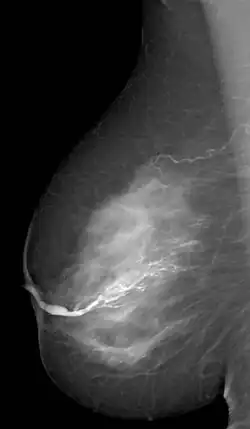

Galactographie sélective des canaux galactophores d'un seul segment.

La galactographie (du grec ancien γαλακτος / galactos, lait et γραφειν / graphein, écrire) est un examen radiologique complémentaire du sein qui permet de visualiser les canaux galactophores.

Il se pratique en injectant un produit de contraste iodé hydrosoluble dans un canal galactophore, puis en réalisant des clichés lors d'une mammographie.

Cet examen permet de mettre en évidence une anomalie à l'intérieur des canaux notamment des images lacunaires, des végétations papillaires intracanalaires multiples pathologiques (tumeur bénigne, papillome)[1].